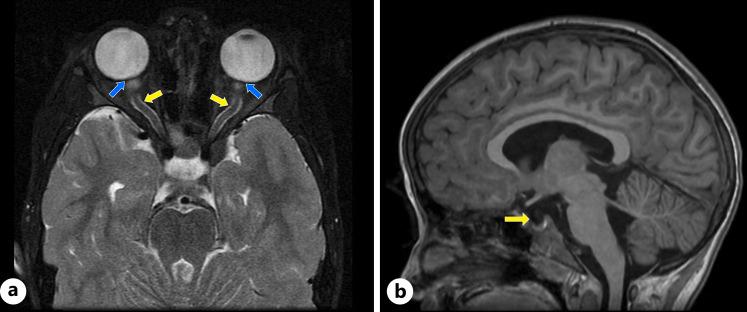

A 6-year-old female presented to our pediatric hospital with binocular horizontal diplopia, headache, fever, malaise, and suspected papilledema 47 days after an embedded tick bite. A diagnosis of Lyme disease had been made 10 days prior in the community based on positive serologies and erythema migrans, but she developed a Jarisch-Herxheimer reaction within 24 h of oral doxycycline, leading to an antibiotic change to amoxicillin. During the hospital admission, an ophthalmological examination revealed papilledema and IH was evidenced by an opening pressure of 36 mm Hg and brain MRI findings. The lumbar puncture revealed pleocytosis and positive cerebrospinal fluid antibodies for . The patient was initially treated with 2 days of ceftriaxone, followed by a 12-day outpatient course of doxycycline for LNB. High doses of acetazolamide (500 mg TID) were needed to achieve symptom control. Two months after her hospital discharge, there was resolution of papilledema and the acetazolamide was weaned.

一名6岁女性在蜱虫叮咬并嵌入皮肤47天后,因双眼水平复视、头痛、发热、不适以及疑似视乳头水肿就诊于我院儿科医院。10天前在社区根据血清学阳性和游走性红斑诊断为莱姆病,但她在口服强力霉素24小时内出现了赫克斯海默反应,导致抗生素更换为阿莫西林。住院期间,眼科检查发现视乳头水肿,脑MRI检查结果及腰穿初压36 mmHg证实存在颅内高压。腰椎穿刺显示脑脊液有核细胞增多以及脑脊液抗体阳性。患者最初接受了2天的头孢曲松治疗,随后门诊接受了为期12天的强力霉素治疗LNB。需要高剂量的乙酰唑胺(500 mg,每日三次)来控制症状。出院两个月后,视乳头水肿消退,乙酰唑胺逐渐减量。